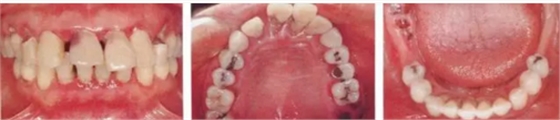

▲圖19-1

40歲,女性。來院主訴為牙齦出血,牙體晃動?;颊卟晃鼰?,因此沒有全身性問題。有明顯的牙周炎,發(fā)生了牙體移動,前牙區(qū)前突。下頜右側磨牙缺失,醫(yī)生認為有必要進行包括牙周修復、正畸治療、種植治療等在內的綜合性治療。

▲圖19-2,3

上下頜咬合面照。

▲圖19-4

X光片。牙槽骨明顯缺失。